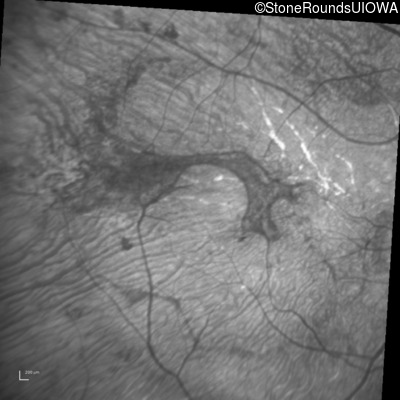

Infrared Fundus Photograph - Right - Light Perception

Exemplar